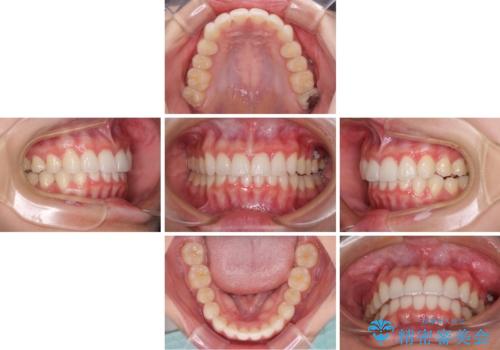

飛び出した前歯と黄ばんだ歯 ホワイトニングしながらマウスピース矯正

- 前歯2本が飛び出してることを気にして来院された患者様です。

全体的に黄ばんだ歯の色も気になるとのことで、マウスピース矯正により飛び出した前歯を治しつつ、ホームホワイトニングを併用して黄ばみを解消していくこととしました。

歯と歯の間を削ることで、飛び出した前歯が引っ込み、スッキリとした口元となりました。

歯の黄ばみも改善され、明るい歯並びとなりました。